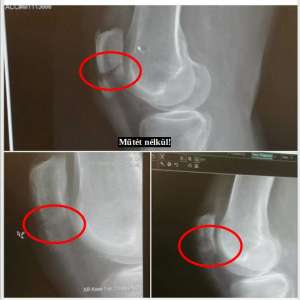

Mára világszerte már több mint 200.000 pozitív tapasztalat mutatja technológiánk rendkívüli hatékonyságát, nem egyszer a csodával határos, már-már szinte meghökkentő tapasztalatokról számolnak be partnereink.

Szeretnénk képzeleted határait tágítani, ehhez kérlek nézd meg oldalunkon a videótárat, illetve keress meg és segítek bejutni titkos Facebook csoportunkba, ahová ezrek töltik fel tapasztalataikat, melyeket szakemberek is értetlenül bámulnak.